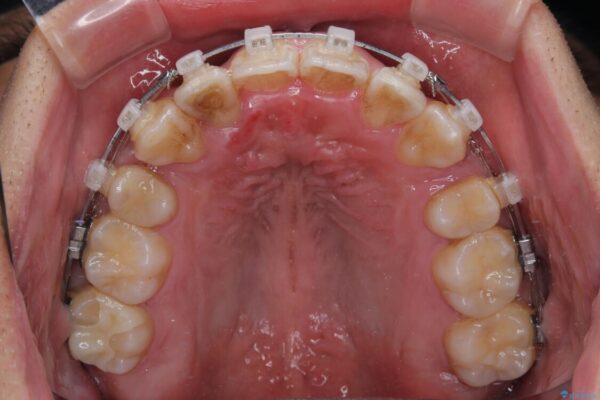

矯正装置は、審美性と費用面のバランスを考慮して、プラスチックブラケットとメタルワイヤーを使用しました。

透明感のあるブラケットを用いたため、従来の金属装置よりも目立ちにくく、日常生活での見た目の不安も軽減できます。

治療途中

• 八重歯と前歯のガタガタを抜歯矯正で治療|クリアブラケット使用例 治療途中画像